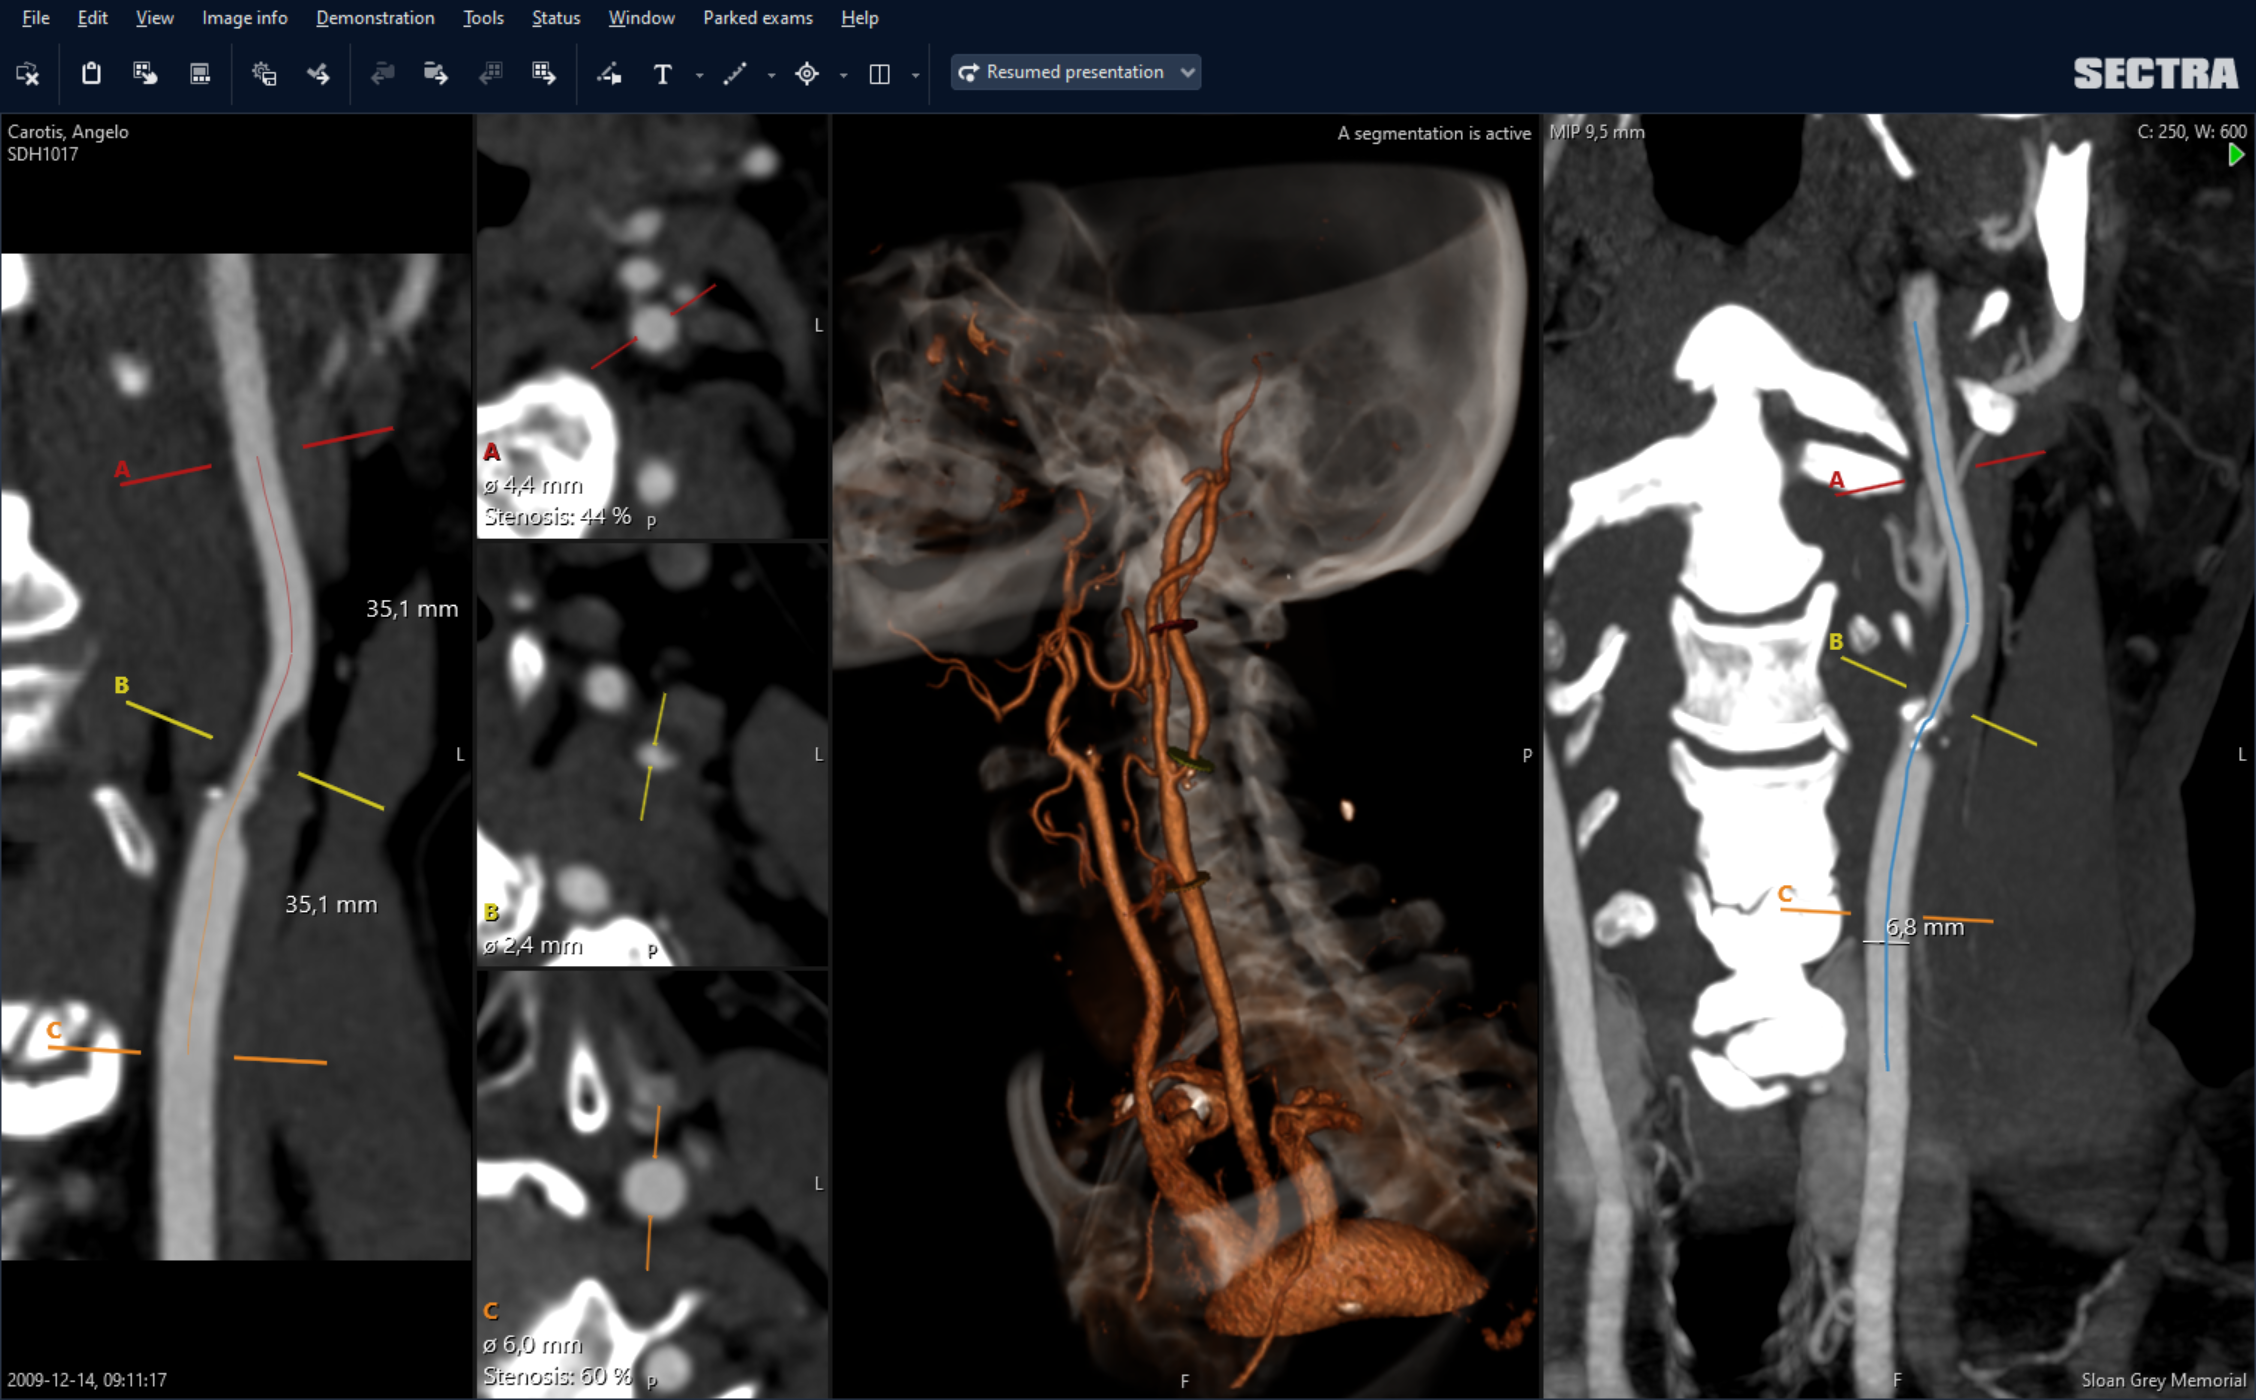

Sectra’s Vessel Analysis application supports the diagnosis, reporting, surgical planning and follow-up of vascular diseases such as stenosis evaluation and EVAR planning. The solution makes it easy to measure vessel diameter and length as well as the degree of stenosis. Measurements, annotations and rotations, etc., can easily be stored using bookmarks, enabling efficient consultations and follow-up.

Now we can provide an exact grade of stenosis in a matter of 30–60 seconds.